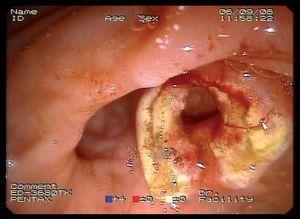

Mujer de 87 años que ingresa en el servicio de cirugía por ictericia, colangitis y pancreatitis aguda. Se instauró tratamiento con sueroterapia y antibióticos, que consiguió la estabilización hemodinámica de la paciente. En una colangiopancreatografía por resonancia magnética (fig. 1) se observó un defecto de repleción en el colédoco distal. Con la intención de desobstruir la vía biliar, se realizó una colangiopancreatografía retrógrada endoscópica (CPRE), empleando sedación consciente con midazolam y dolantina. En la endoscopia, la ampolla de Vater se encontró muy abultada, con un orificio en el que parecía entreverse una coledocolitiasis (fig. 2). Se realizó una esfinterotomía biliar amplia (fig. 3) y se extrajo una coledocolitiasis de 13 mm de diámetro máximo, que estaba impactada en la ampolla (fig. 4). La evolución de la paciente fue satisfactoria.

Fig. 2